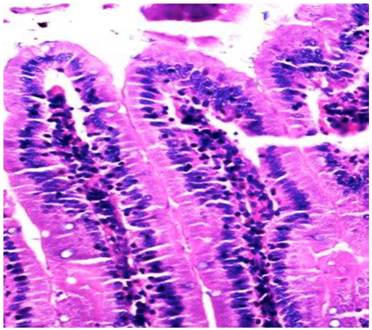

Figure 2

Jejunum of group C; Microscopic examination showed goblet cell decrements (hematoxylin and eosin, x20).

In the group C rats, subjected to 3 months of oral ABS administration, inflammation, goblet cell loss and intra-epithelial lymphocyte infiltration were observed in all of the rats. Mixed inflammation included eosinophil, neutrophil and lymphocyte that were observed in the duodenum (50 %), jejunum (50 %), and caecum (66.6 %). Eosinophilic and neutrophilic inflammations of the rectum were also evident (100 %). Inflammations were observed in the mainly lamina propria. Loss of goblet cell reductions of 66 % in the duodenum and 100 % in the jejunum were detectable in this group with longest exposure to ABS. Intra-epithelial lymphocyte infiltration in the duodenum, jejunum and caecum were found in all of the rats in this cohort (group C). Control group (group D) did not demonstrate any pathological changes of the liver or gastrointestinal tract.

The magnitude and frequency of inflammation was greater in groups B and C in comparison to group A (P= 0.001). Loss of goblet cell and intra-epithelial lymphocyte infiltration were not significantly different between groups A and B (P= 0.308 and P= 0.189, respectively). However, there was significantly higher intra-epithelial lymphocyte infiltration in group C than in group A (P=0.04). The histopathological appearances and the parameters for the inflammation, loss of goblet cell and intra-epithelial lymphocyte infiltration are depicted in Table 1.